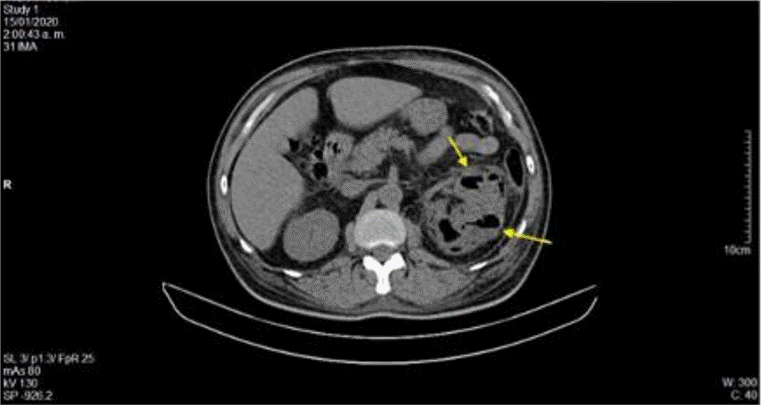

La ecografía abdominal total mostró hallazgos sugestivos de PNE izquierda (Figura 1), por lo que se solicitó valoración por urología; este servicio indicó continuar con la misma terapia antibiótica y realizar UROTAC que mostró microlitiasis renal bilateral, litiasis ureteral izquierda y proceso infeccioso inflamatorio con presencia de gas en el riñón izquierdo, lo que indicó diagnóstico de PNE izquierda tipo 2 (Figuras 2 y 3). Ante los hallazgos radiológicos y el reporte de urocultivo positivo para Escherichia coli multisensible, se decidió hacer rotación de cubrimiento antibiótico a carbapenémicos debido al alto riesgo de mortalidad.

Fuente: documento obtenido durante la realización del estudio

Figura 2 UROTAC en el que se evidencia asimetría renal, riñón izquierdo aumentado con evidencia de múltiples zonas de acumulación de gas peri y pararrenal.